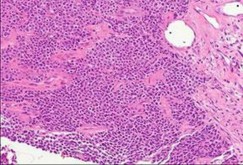

A 15-year-old male presents with deep knee pain awakening him at night. Radiographs show a permeative destructive lesion in the distal femoral metaphysis with a 'sunburst' periosteal reaction and Codman's triangle.

Biopsy confirms high-grade conventional osteosarcoma. What is the most critical prognostic factor for long-term overall survival in this patient?

Explanation

For localized high-grade osteosarcoma, the most important prognostic indicator is the histologic response to neoadjuvant chemotherapy. This is evaluated during the definitive resection. A 'good response' is typically defined as greater than 90% or 99% tumor necrosis. Patients who achieve this level of necrosis have a significantly improved disease-free and overall survival rate compared to 'poor responders' who have extensive viable tumor cells remaining.